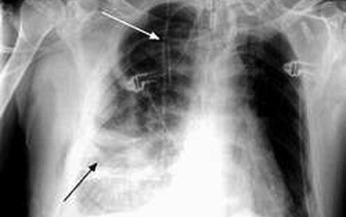

Viêm mủ màng phổi là tình trạng viêm tràn mủ trong khoang màng phổi. Bệnh diễn tiến cấp tính, bán cấp và mạn tính, gây tổn thương màng phổi toàn thể hay khu trú. Mầm bệnh có thể là vi khuẩn thường, trực khuẩn lao hoặc ký sinh trùng như amip...

Viêm mủ màng phổi (VMMP) là sự tràn mủ trong khoang màng phổi. Dịch là mủ thật sự hoặc là chất dịch đục hay màu nâu, nhưng bao giờ cũng có xác bạch cầu đa nhân là thành phần chính của mủ.